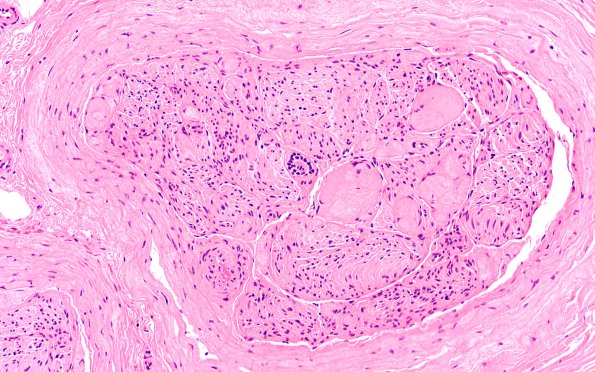

Washington University Experience | PERIPHERAL NEUROPATHY | 19 TRAUMATIC INJURIES | 22A3 Median nerve compression (Case 22) H&E 20X 1A

22A2-4 There is marked expansion and fibrosis of the perineurium. In addition, there are numerous atypical Renaut bodies which appear more fibrotic than the typical wispy constructs seen in most cases in which they are encountered. Since Renaut bodies are often described to result from chronic compression the clinical scenario appears particularly valid in this case. Some vessels also appear thickened but there is no evidence of angionecrosis.